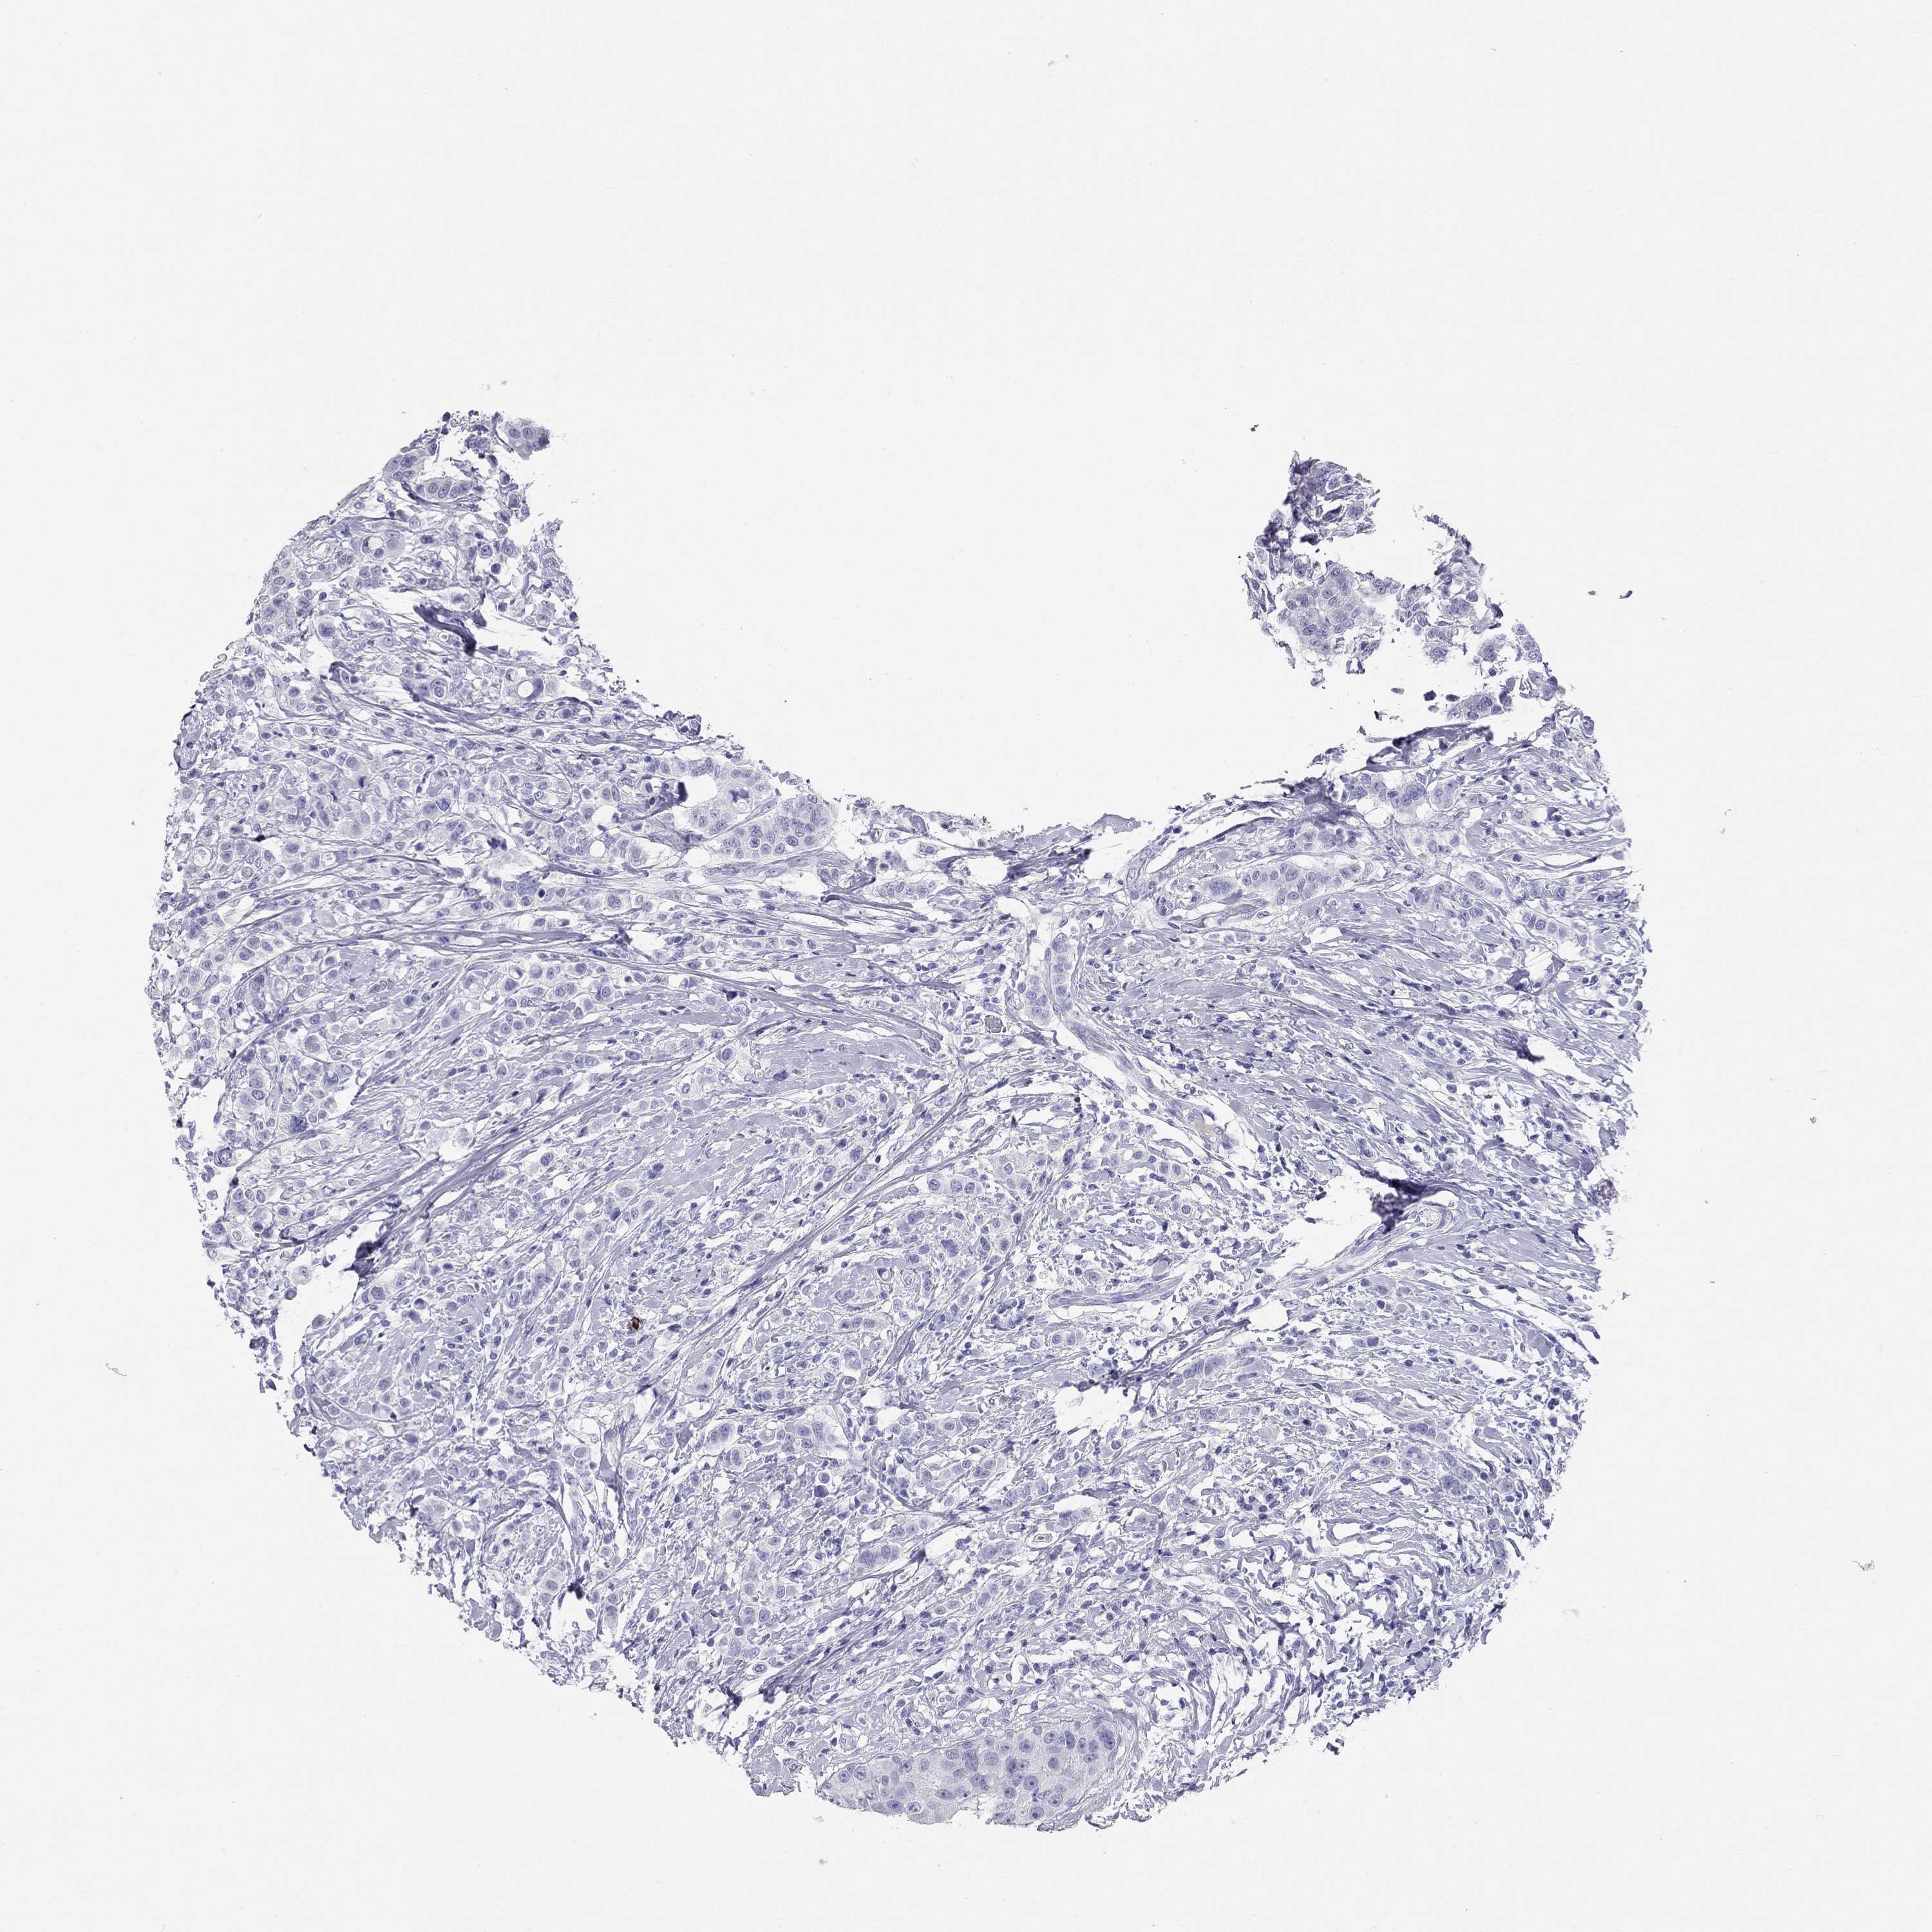

CANCER BREAST CANCER Show tissue menu

BRCA TCGA BRCA VALIDATION PROTEIN EXPRESSION

KLRG1 is not prognostic in Breast Invasive Carcinoma (TCGA)